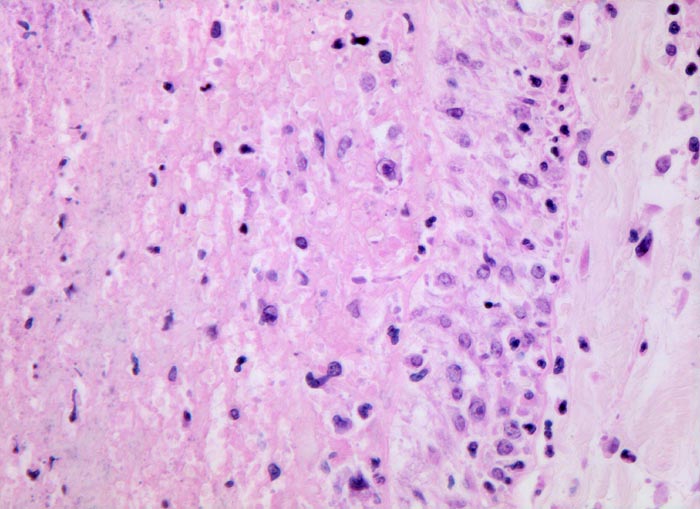

• Scharf begrenzte dreiecksförmige hämorrhagische Nekrose des Lungenparenchyms.

• Alveolen gefüllt mit zerfallenden Erythrozyten, Kerntrümmern und Fibrin.

• Lungengerüst erhalten im Randbereich der Nekrose, nicht mehr erkennbar im Zentrum.

• Abgeblasste Zellkerne in der Nekrosezone.

• Pulmonalarterienast mit nicht wandhaftendem Thrombembolus am Rand des Infarktes.